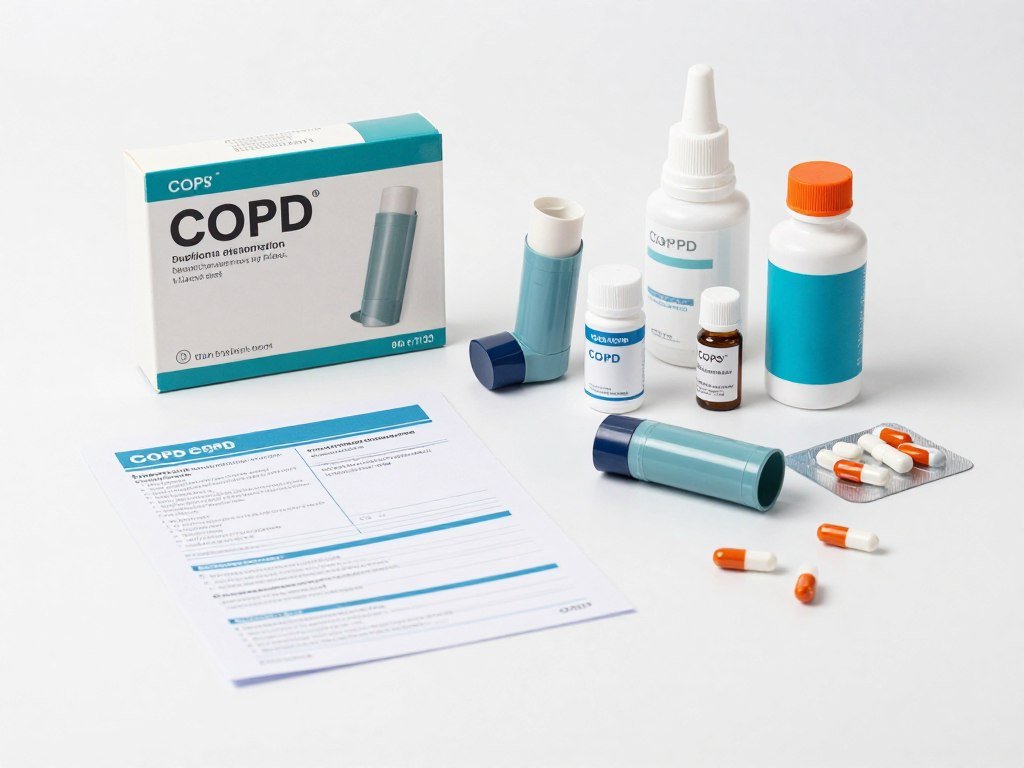

Primary Treatment Approaches

Medication Therapy

Bronchodilators open airways and ease breathing difficulties. These medications reduce inflammation and help clear mucus from lungs.

Inhaled corticosteroids reduce inflammation in airways. Combined therapies work synergistically for better symptom control.

Oxygen Therapy

Supplemental oxygen improves blood oxygen levels. This treatment prevents complications from chronic low oxygen saturation.

Portable concentrators enable mobility. Modern technology allows oxygen therapy during daily activities and travel.

Pulmonary Rehabilitation

Structured exercise programs strengthen respiratory muscles. Breathing techniques improve oxygen efficiency during activities.

Education components empower patients. Knowledge about disease management leads to better adherence and outcomes.

Medication Management

Personalized medication plans utilizing the latest bronchodilators and anti-inflammatory treatments for symptom control.